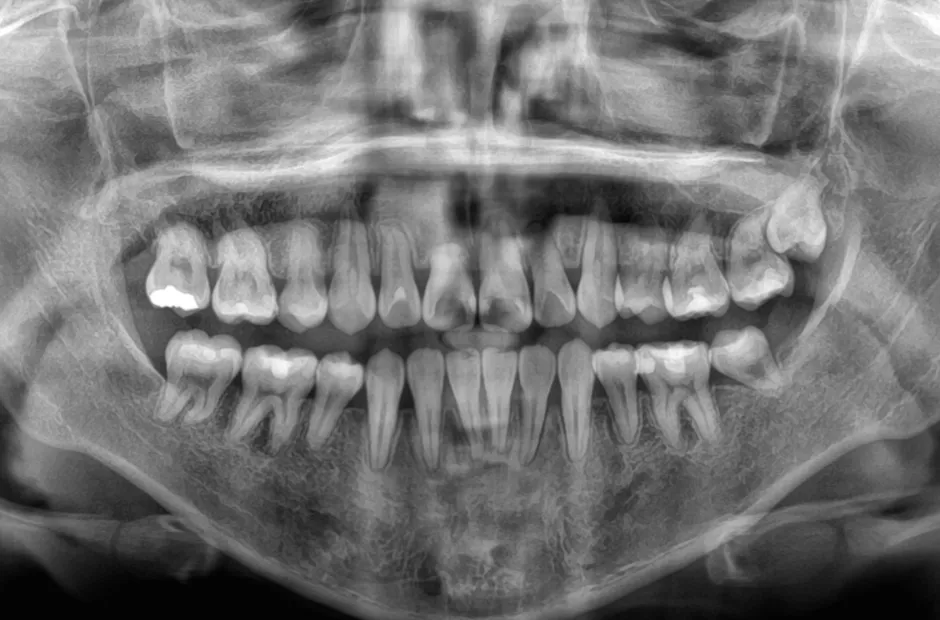

| 診断名・主訴 | 叢生 |

|---|---|

| 年齢・性別 | 43歳・女性 |

| 治療期間・回数 | 2年7か月 27回 |

| 治療に用いた主な装置 | 舌側矯正 |

| 抜歯部位 | 両顎4,4 |

| 治療費 | 100万円(税抜) |

| リスク・副作用 | 装置による違和感・疼痛・歯肉退縮・歯根吸収・虫歯のリスクなど |

治療前

治療中

治療後